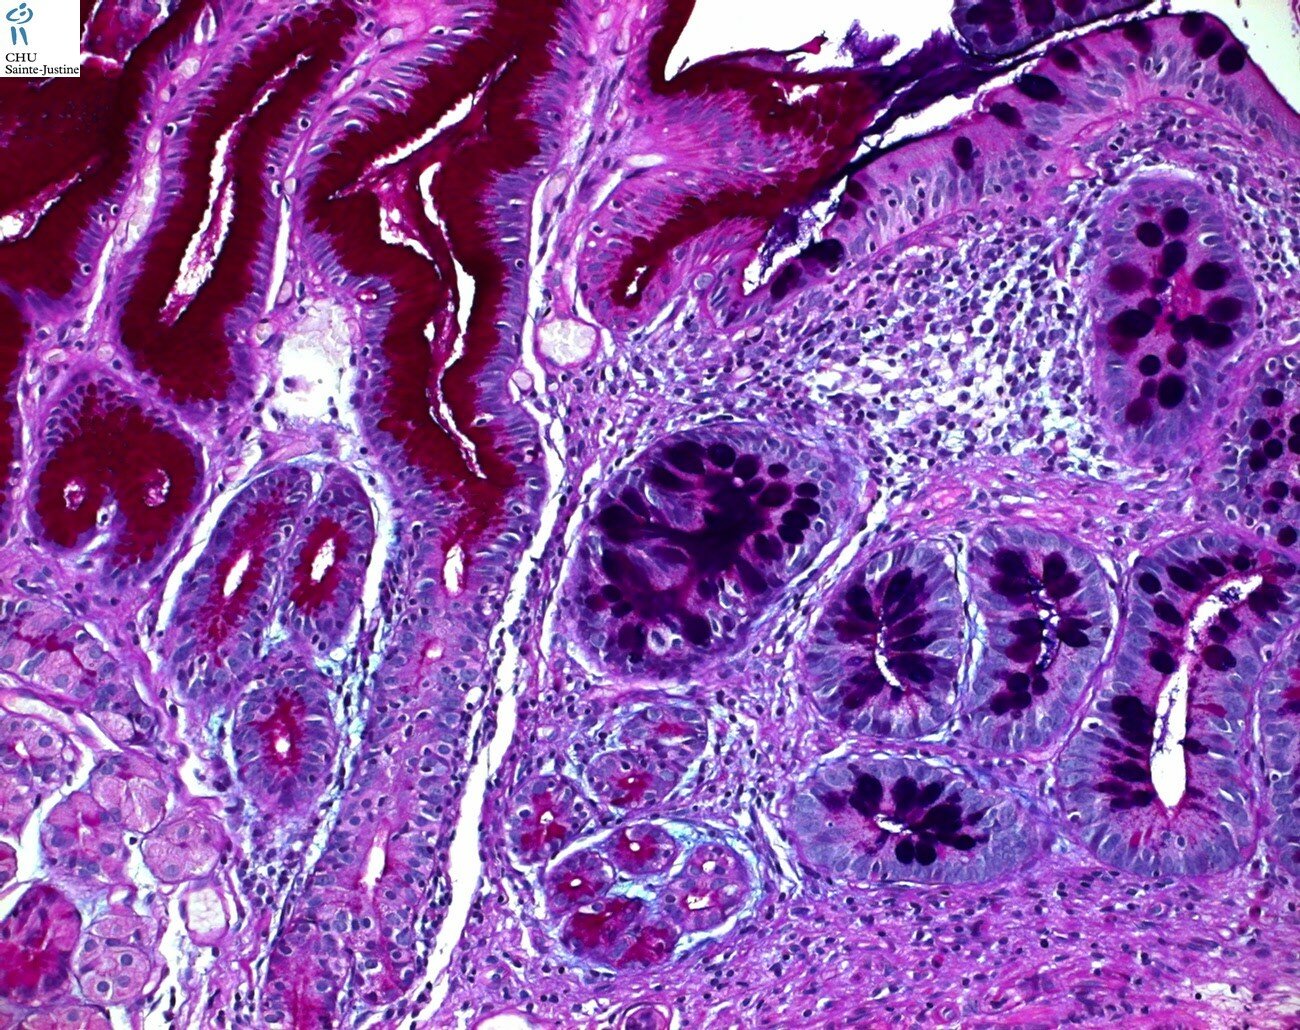

intestinal metaplasia in stomach